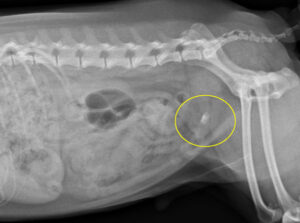

5~6歳以上の去勢手術をしていないオス犬に多い病気ですが、メス犬や去勢した犬に起こることもあります。お尻の筋肉が萎縮した結果、筋肉の隙間から直腸や膀胱が皮膚の下にとびでてしまいます。これにより便が出にくくなったり膀胱炎になったりします。手術をすることで機能回復および今後の致死的な状況を回避することができます。当院では去勢手術→結腸固定→前立腺固定→骨盤隔膜構成筋の縫縮→内閉鎖筋フラップ→浅臀筋フラップの順で通常腹側・臀部左右両側同時に行います。また老化以外に、筋肉が萎縮する原因があったり、腹圧がかかる原因があったりする場合も多いので、再発防止のためそれらの診断・治療も重要です。今回のワンちゃんも無事手術も終わり元気に退院しました。よかったね。